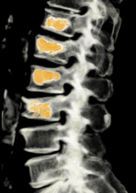

Die Mehzahl der behandlungsbedürftigen Erkrankungen finden sich im Bereich der Brust- und Lendenwirbelsäule. Von Verschleißerkrankungen ist insbesondere der Übergag zum Becken betroffen, Verletzungen treten eher am Übergang zur Brustwirbelsäule auf. Deformitäten, Tumore und Metastasen, Infektionen oder rheumatische Erkrankungen entstehen in allen Bereichen.

Die Wirbelsäule als zentrales Achsenorgan des Körpers hat vielfältige Funktionen. Unter anderem nimmt sie die gesamte Last des Körpers auf, ist wesentlich an der Statik sowie Bewegung beteiligt und beinhaltet das Rückenmark sowie der Verteilung der Nerven. Somit können Erkrankungen der Brust- und Lendenwirbelsäule neben reinen Schmerzsyndromen erheblich Auswirkungen nach sich ziehen. Auch hier ist durch engen Kontakte zu verschiedenen Organsystemen häufig ein interdisziplinäres Vorgehen erforderlich.

Die Mehrzahl von Erkrankungen der Brust- und Lendenwirbelsäule kann konservativ oder interventionell-schmerztherapeutisch behandelt werden. Dennoch gibt es viele Situationen, die ein operatives Vorgehen erforderlich machen. Dies kann neben Schmerzen insbesondere bei bestehenden oder drohenden Instabilitäten oder Rückenmarks- bzw. Nervenschädigungen der Fall sein oder bei Erkrankungen von Kindern.